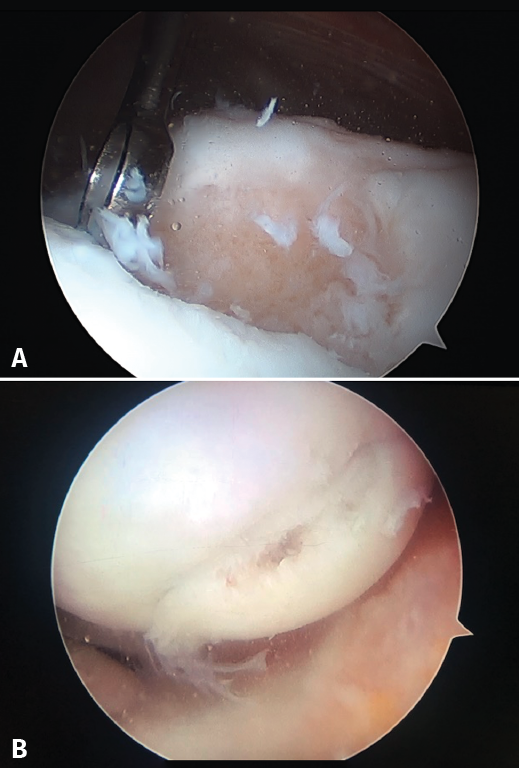

Although cartilage damage is most often of idiopathic or degenerative origin, joint cartilage injuries are also frequently caused by traumatisms (Figure 1A), i.e., joint trauma, followed by osteochondritis dissecans (OCD)(1,2)(Figure 1B).

Figure 1. Arthroscopic view of osteochondritis dissecans of the external femoral condyle.

The chondral defects may be partial or complete, depending on whether the full thickness of the cartilage is affected, with involvement of the subchondral bone. In this case a repair mechanism is activated that does not produce normal cartilage but rather repair tissue lacking the biomechanical characteristics of healthy hyaline cartilage, due to a decrease in type II collagen, which is replaced by type I collagen. In addition, the chondrocytes are replaced by fibroblasts, which are unable to produce an extracellular matrix with the adequate concentration of type II collagen(3,4)(Figure 2).

Figure 4. Arthroscopic views of the Outerbridge chondral lesion grades. A: grade I lesion; B: grade II lesion; C: grade III lesion.

Figure 4 shows arthroscopic images of lesions corresponding to grade II (Figure 4A), grade III (Figure 4B) and grade IV (Figure 4C).